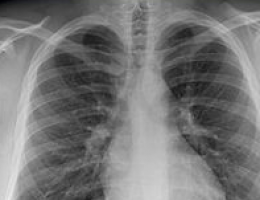

Para el estudio, los investigadores de Moffitt utilizaron datos del Ensayo Nacional de Detección de Pulmones (NLST, por sus siglas en inglés), un estudio que compara dos métodos de detección de cáncer de pulmón: la tomografía computarizada de baja dosis y la radiografía de tórax estándar.

Generaron características radiológicas de los pacientes del NLST a los que se les diagnosticó cáncer de pulmón durante su examen.

Las características, como el tamaño, la forma, el volumen y las características de textura, se calcularon desde dentro (intratumoral) y alrededor (peritumoral) de sus tumores de cáncer de pulmón.